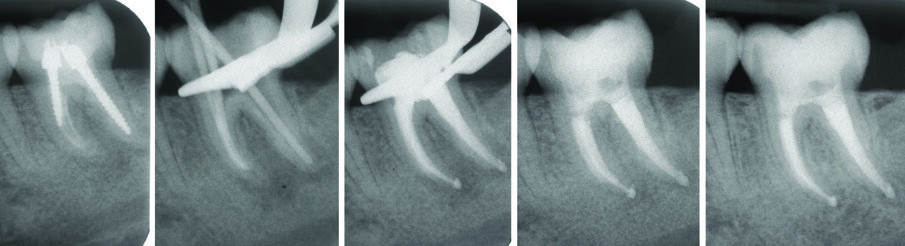

All’esame radiografico le otturazioni appaiono dense ed omogenee, la guttaperca mostra un buon adattamento alla morfologia endodontica, determinando un buon riempimento delle irregolarità del sistema canalare. Sono stati evidenziati la presenza di canali laterali ed uscite apicali multiple. Figg. 8a-8e molare superiore, Figg. 9a-9e molare inferiore, Figg. 10a-10c molare superiore, Figg. 11a-11d anatomie complesse premolare curvo e Figg. 12a-12d ottavo.

Fig. 11 - Terapia canalare 3.8.

Fig. 12 - Ritrattamento canalare 1.6 controllo a 10 anni.